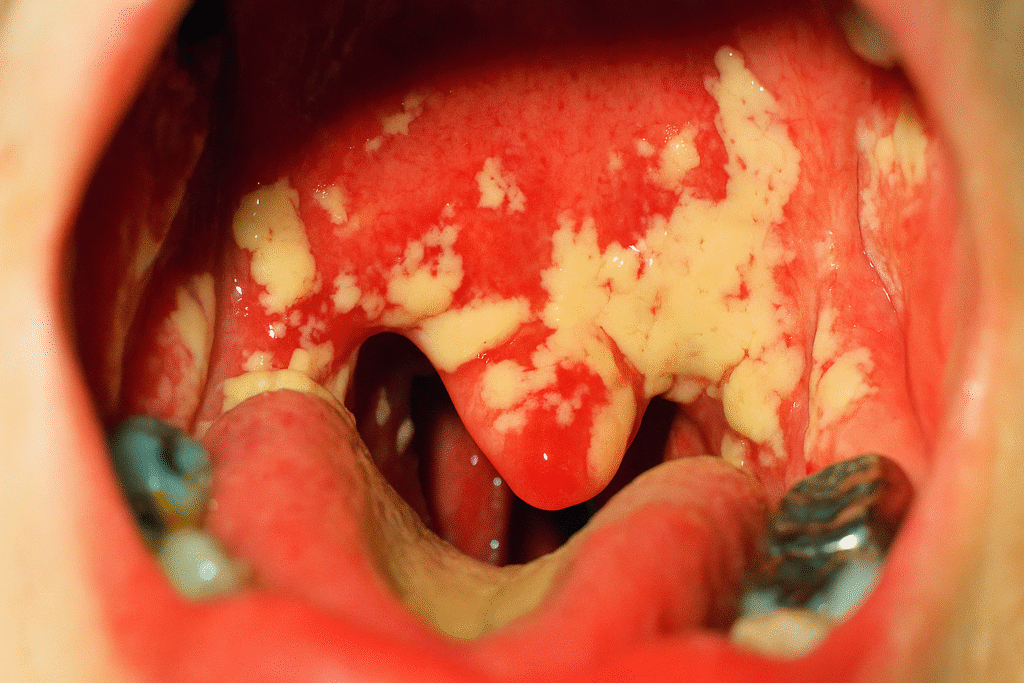

Síntomas comunes

- Manchas blancas o amarillas en la lengua, mejillas, encías o labios.

Un médico puede diagnosticar la candidiasis oral observando las lesiones en la boca. En algunos casos, se realiza una biopsia o un cultivo de garganta para confirmar la infección.